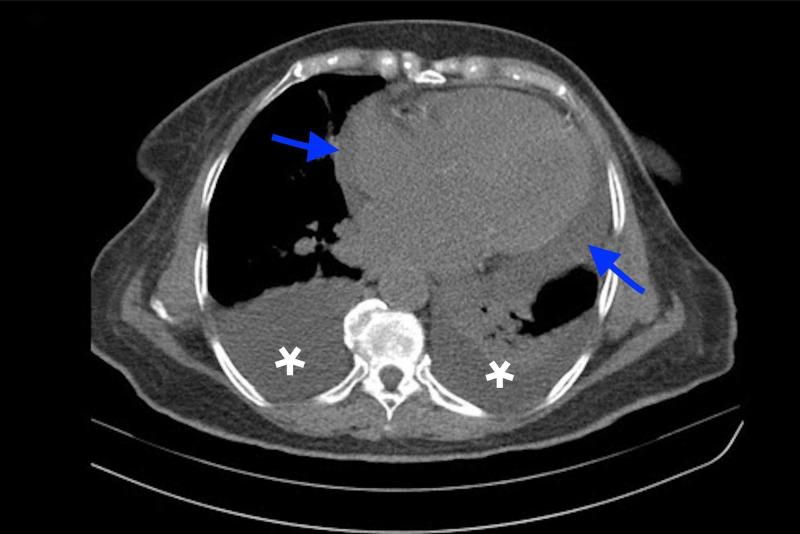

Hydralazine induced lupus syndrome (HILS), a form of Drug-Induced Lupus (DIL), was first reported in 1953. Since then, studies have shown an increasing incidence of HILS. It presents with lupus-like symptoms such as arthralgia, fever, chest pain, anorexia, fatigue, petechiae, and rash. Though rare, HILS may initially present with pericardial effusion. Lab findings of HILS usually show positive anti-nuclear antibody (ANA) in >95% of cases, antihistone abs in >95% of cases, rheumatoid factor ab in 20%, and anti-double-strand DNA in <5%. Herein we present a case of HILS which initially presented with a seronegative ANA and pericardial effusion. An 82-year-old woman who presented with shortness of breath was found to have bilateral pleural effusion and pericardial effusion. Common etiologies of pericardial effusion have been ruled out, after careful review of her home medications, hydralazine was suspected to be the culprit of her pericardial effusion. Initial ANA testing was negative, however given high clinical suspicion autoimmune disease screening was done revealing positive anti-histone antibodies. Hydralazine was deemed to be the etiology of her pericardial effusion which led to the discontinuation of the drug. Serial echocardiography revealed no recurrence of the effusion.

肼屈嗪诱发的狼疮综合征(HILS)是药物性狼疮(DIL)的一种形式,于1953年首次报道。从那时起,研究表明HILS的发病率在不断上升。它表现出类似狼疮的症状,如关节痛、发热、胸痛、厌食、疲劳、瘀点和皮疹。虽然罕见,但HILS最初可能表现为心包积液。HILS的实验室检查结果通常显示,超过95%的病例抗核抗体(ANA)呈阳性,超过95%的病例抗组蛋白抗体呈阳性,20%的病例类风湿因子抗体呈阳性,不到5%的病例抗双链DNA呈阳性。在此,我们报告一例最初表现为ANA血清阴性和心包积液的HILS病例。一名82岁出现呼吸急促的女性被发现有双侧胸腔积液和心包积液。在仔细检查其家庭用药后,排除了心包积液的常见病因,怀疑肼屈嗪是其心包积液的罪魁祸首。最初的ANA检测为阴性,但鉴于高度临床怀疑,进行了自身免疫性疾病筛查,结果显示抗组蛋白抗体呈阳性。肼屈嗪被认为是其心包积液的病因,导致停用该药物。系列超声心动图显示积液未复发。